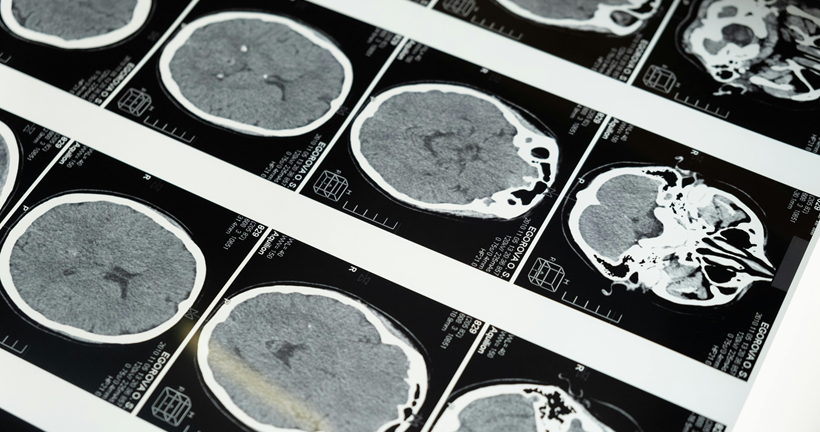

La enfermedad de Alzheimer es la causa más frecuente de demencia y se caracteriza por la acumulación progresiva de placas de beta-amiloide en el cerebro, un proceso que puede comenzar hasta 20 años antes de que aparezcan los primeros síntomas. En este contexto, la medicina nuclear ha revolucionado el diagnóstico gracias a técnicas como la tomografía por emisión de positrones (PET) con trazadores específicos, entre ellos el [18F]Florbetaben, que permite visualizar directamente estos depósitos amiloides in vivo.

El estudio analizado compara dos formas de interpretar estas imágenes PET en pacientes con sospecha de Alzheimer: la evaluación visual, basada en la experiencia de especialistas, y un método más objetivo denominado escala Centiloide, que cuantifica la carga de amiloide en una escala estandarizada de 0 a 100. Esta comparación se realizó en una cohorte de 208 pacientes con deterioro cognitivo leve o demencia leve, seguidos clínicamente durante varios años, lo que permitió establecer un diagnóstico final fiable basado en su evolución.

Los resultados muestran que ambos métodos son altamente precisos y presentan una concordancia muy elevada. En el 95% de los casos, la interpretación visual y la cuantificación mediante Centiloides coincidieron entre sí y con el diagnóstico clínico final. La evaluación visual alcanzó una sensibilidad y especificidad cercanas al 97%, lo que confirma que sigue siendo una herramienta muy sólida en la práctica clínica diaria. Por su parte, el análisis cuantitativo mostró una especificidad aún mayor, lo que sugiere que puede ser especialmente útil para confirmar la ausencia de enfermedad.